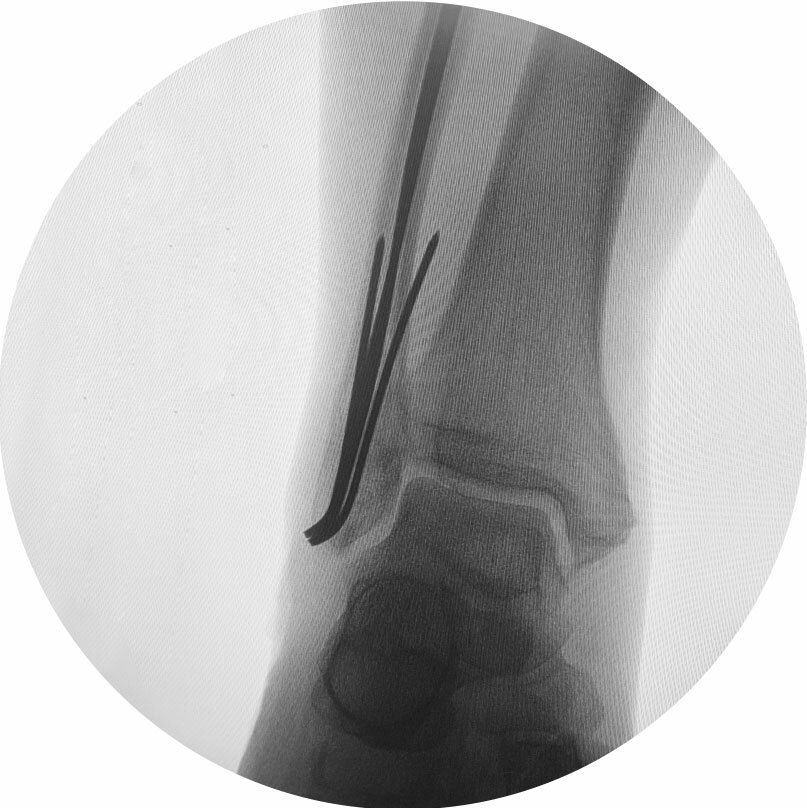

Лечение перелома лодыжки | L-Clinic